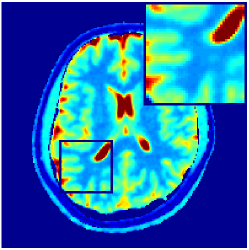

Two sets of experiments were conducted here: first, we used the 2D and 3D acquisition sequences for scanning a healthy volunteer’s brain (real-world acquisitions). Figures 6 and 7 display the parametric maps reconstructed from 2D spiral and radial readouts. We computed the T1, T2 and proton density (PD) maps using baseline reconstruction algorithms ZF, VS, LR, FLOR, AIR-MRF and our proposed LRTV. While baselines use DM either for quantitative inference or also during reconstruction (i.e. AIR-MRF), we further compare the DM-free LRTV’s performance when cascaded to DM, KM and MRFResnet for quantitative inference. For the 3D spiral acquisitions we compared LRTV and its closest competitor VS in Figure 8. Outcomes from other tested algorithm are displayed in the supplementary materials (Figure S5). Since FLOR does not use dimensionality-reduction, our system ran out of memory during 3D reconstruction; hence results are not reported in this case.

VI-E1 Discussion

The LRTV-DM and LRTV-MRFResnet perform on par, and both outperform all tested baselines for reconstructing T1, T2 and PD maps in all acquisition schemes. This can be observed both visually in Figures 6, 7, 8, S2 and S3, and quantitatively in Table IV across all tested metrics. Other baselines were unable to successfully remove the under-sampling artefacts in TSMIs, and these errors propagated to the parameter inference phase and resulted in inaccurate maps. Temporal-only priors incorporated within LR are shown insufficient to regularise the inverse problem and LR sometimes (e.g. 2D spiral acquisitions) can admit solutions with even stronger artefacts than the model-free ZF baseline. This issue was previously studied for other non-Cartesian MRF readouts that similar to our spiral/radial trajectories, miss to sample the corners of the k-space in all timeframes (see section 2.2.2 and figure 2 in [19]). In the absence of reference for the k-space corners information, the LR iterations despite minimising the objective can converge to solutions with high-frequency artefacts, as visible in the computed maps. This highlights the need for adding an appropriate spatial-domain regularisation. FLOR reduces the LR’s artefacts but this improvement is limited because the suggested nuclear norm penalty does not incorporate an explicit spatial regularisation. Further for reducing artefacts, FLOR can introduce an undesirable bias in the computed T1/T2 maps e.g. see error maps in Figures S2 and S3. The non model-based VS baseline incorporates spatial regularisation and results in spatially smoother maps than ZF and LR, but it is unable to output artefact-free images. Further and consistent with our in-vitro experiment, we observe that VS overestimates the T2 values (e.g. in White and Grey matter regions) in tested 2D acquisitions i.e. the spatial regularisation trades off agains the quantification accuracy. The model-based AIR-MRF adds spatial regularisation through 2D/3D low-pass Gaussian filters however this trades off the sharpness of the computed maps and can increase the errors at the tissue boundaries (we searched Gaussian spreads that keep the blurs and high-frequency artefacts minimal). For our acquisition readouts, Gaussian filters performed better than disk filters of [19] for avoiding strong Gibbs artefacts. On the other hand, the spatiotemporally regularised LRTV greatly improves the TSMI reconstructions i.e. 4 dB enhancement compared to the closest competitor baseline (Table IV). This enables computing accurate and aliased-free multi-parametric inference using DM or the DM-free learning-based alternative MRFResnet as visible in Figures 6, 7, 8, S2 and S3. MRResnet and DM score competitive quantitative inference results i.e. T1 and T2 MAPE less than 5% and 9%, respectively (Table IV). KM also outputs comparably accurate T1 maps, however this shallow learning model despite having a model size larger than MRFResnet, is unable to learn accurate T2/PD quantification and it results in poor estimated maps, consistent with our observations in section VI-C.